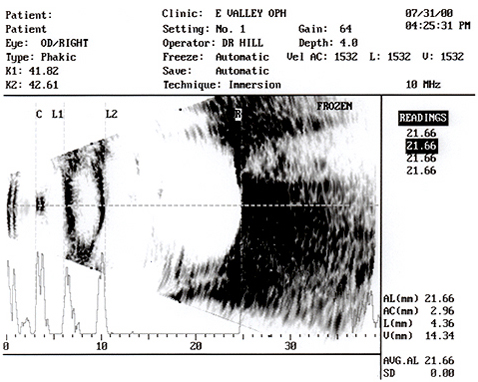

Figure E - The B-scan is oriented horizontally with the vector A-scan

going through the center of the cornea (C), anterior lens (L1) and posterior

lens (L2).

With this alignment, the vector A-scan will intersect the retina at

the approximate center of the macula, just below the void of the optic nerve.

An immersion echogram through the posterior fundus is obtained using a horizontal axial B-scan approach. The goal is to center the cornea and lens echoes in the echogram while simultaneously displaying the optic nerve void near or slightly above the center. The A-scan vector is then adjusted so as to pass through the middle of the cornea as well as the anterior and posterior lens echoes. Such alignment assures that the vector will intersect the retina in the region of the fovea. This technique is particularly important when the macula lies on the sloping wall of the staphyloma.